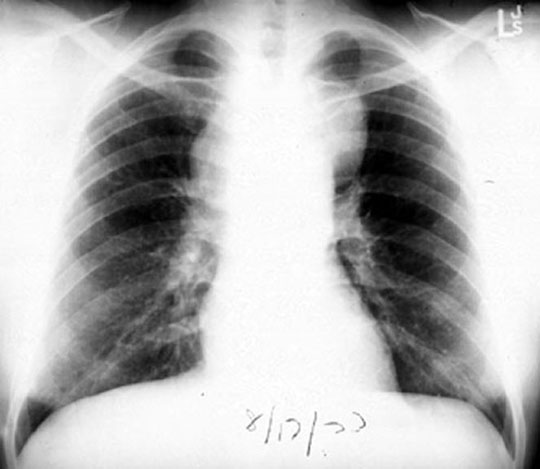

48 year old female presents with low grade fever, dry cough and 12 lbs weight loss in the past two months.

Findings:

• Mediastinal adenopathy

• Particularly in anterior mediastinum

• Bilateral and asymmetric

• Large and bulky

Diagnosis

Anterior Mediastinal Mass

Lymphoma